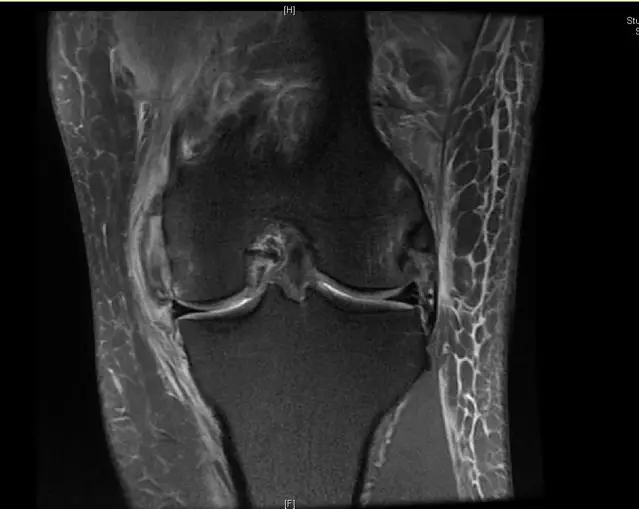

后交叉韧带断裂

这个病例韧带连续性中断松弛,尤其上止点的信号增高;从这个层面来看它的上止点形态不完整,部分信号增高;从这个层面可以看到,韧带的形态信号增粗,松弛,信号也是增高的,所以这个病例可以诊断为后交叉韧带断裂。